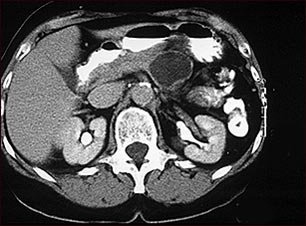

Adenoma quístico del páncreas; TC

Esta TC del abdomen superior muestra, en la parte superior derecha de la imagen, un gran quiste en el páncreas (adenoma quístico del páncreas).